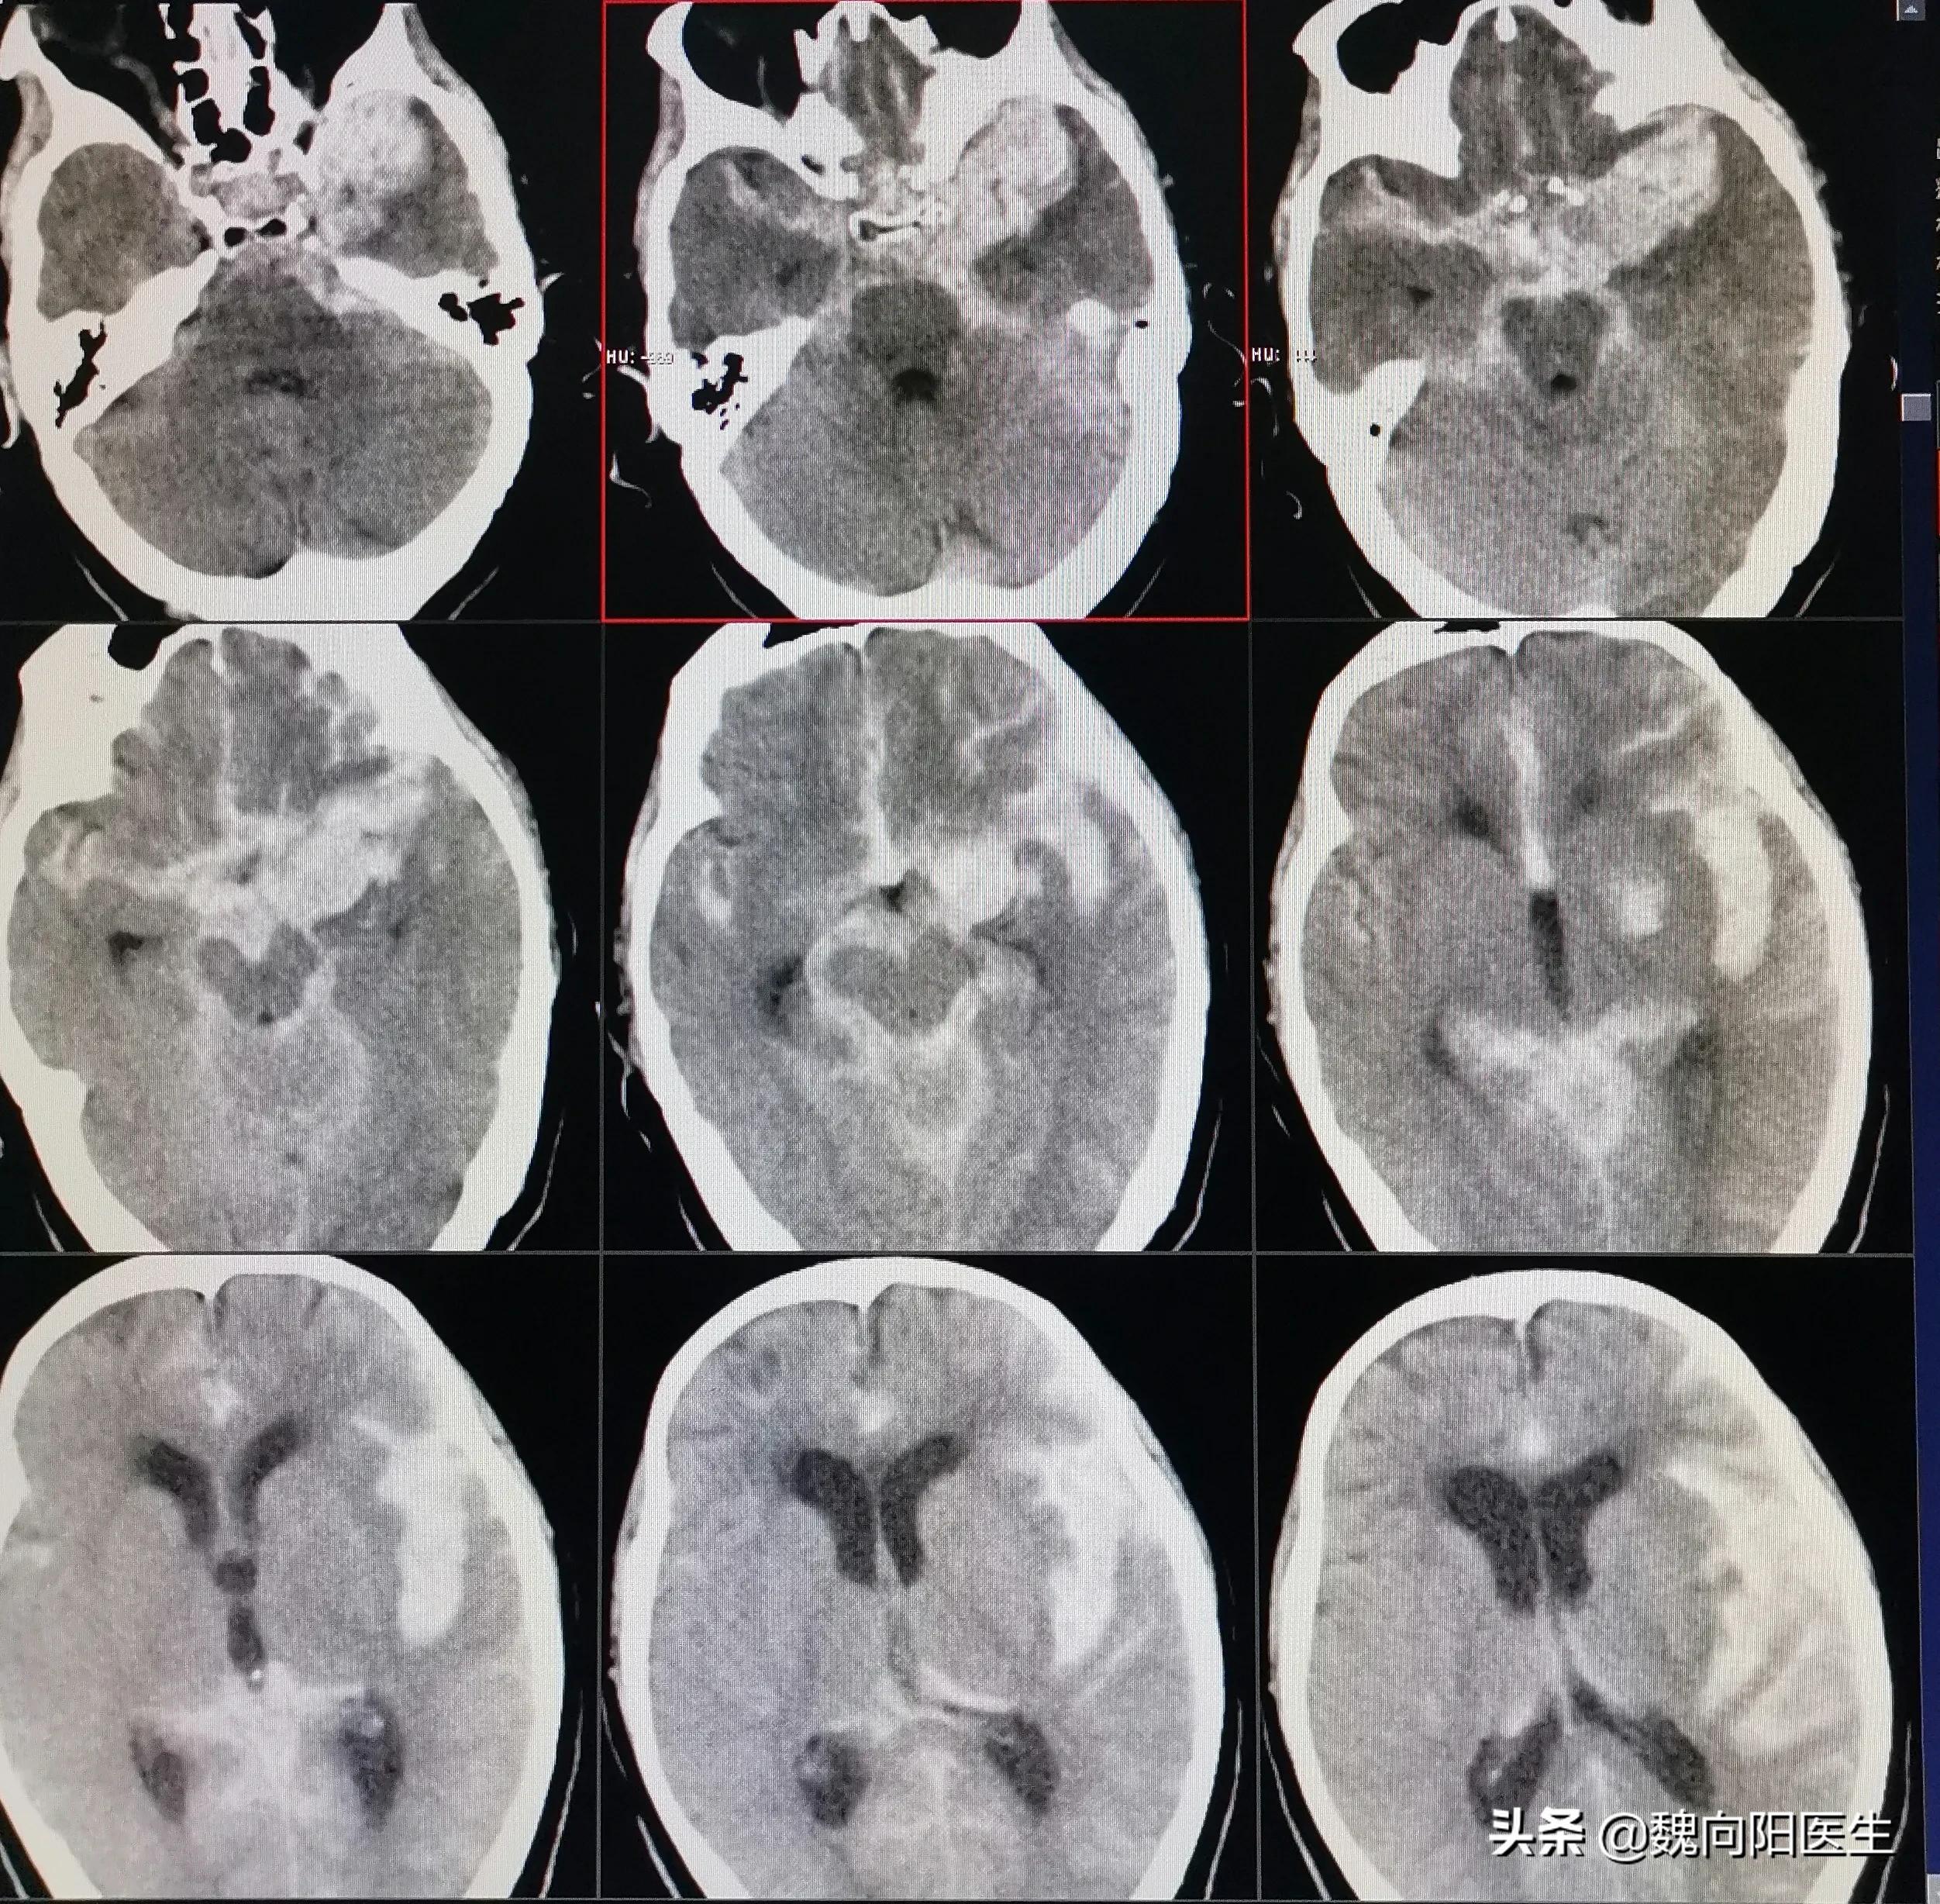

当送至我院后,再次复查头CT发现:“患者蛛网膜下腔出血较前增多,伴双侧侧脑室扩大”,且患者和昏迷状态更加严重,出现了呼吸困难情况,在急诊立即给予经口气管插管术,给予呼吸机辅助通气治疗。患者目前的意识状态逐渐加重,考虑是患者急性蛛网膜下腔出血并发急性脑积水导致,且脑积水情况进行性加重,立即给予侧脑室穿刺引流,改善脑室积水。诊断周某是自发性蛛网膜下腔出血,不排除患者出血原因是颅内动脉瘤破裂导致,因此建议立即行脑血管造影检查,明确发病原因,并给予有针对性的治疗。经患者家属同意后,立即联系介入导管室,给予全麻下脑血管造影发现:“小脑后下动脉动脉瘤”,经过分析考虑该动脉瘤为责任病灶,如果不处理该动脉瘤,则第二次出血风险高,且一旦再次出血后症状会更加严重,甚至危及生命。